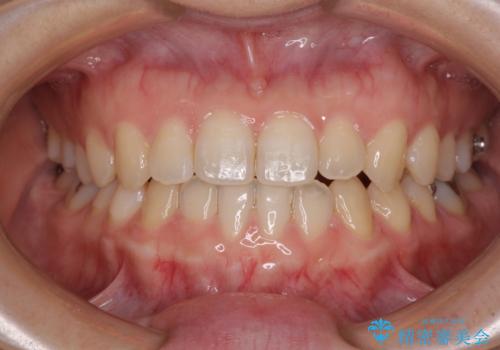

前歯のクロスバイト インビザラインによる矯正治療

- 前歯のクロスバイトとデコボコを気にして来院された患者様です。

骨格的に下顎前突傾向であるため、自己管理が煩わしくないようであれば、インビザラインによる矯正治療がお勧めとなります。

インビザラインを用い、下顎歯列を後方に移動させながら全市の被蓋を改善し、歯並びを整えていくこととしました。

途中マウスピースが使用できず、来院されない期間があり、治療期間は長くかかりましたが、無事に治療を終えることができました。